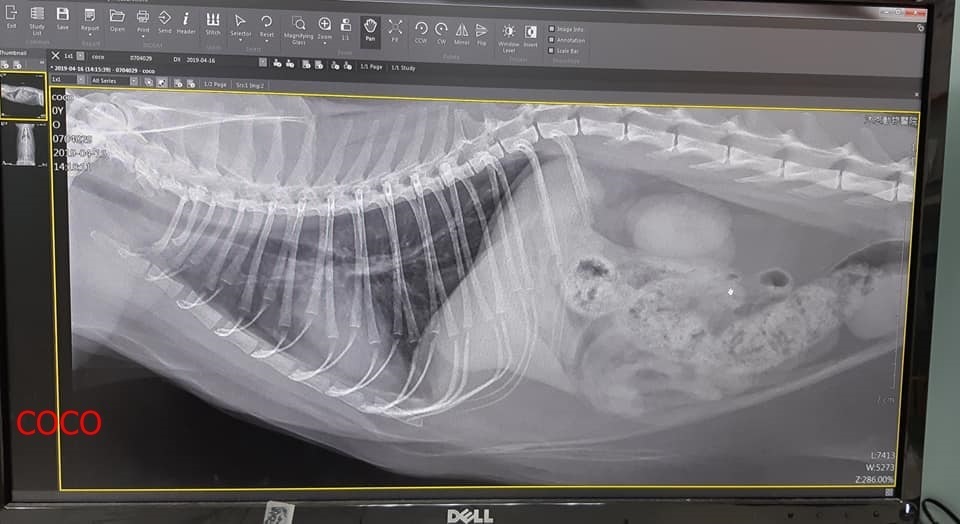

2019年4月間照護員發現COCO一直咳嗽,因此約診沐恩醫院進行檢查,經過血檢,X光,並沒發現肺部有何異常,血檢指數的白血球稍高其他指數都沒有問題,只要先一週藥再觀察即可。

本筆醫助是COCO於4月16日在沐恩醫院的醫療費用,請大家一起幫忙可愛的COCO妹妹,謝謝大家

む醫療め

4/16 CoCo 沐恩 林文傑醫師

體重:5.98kg

一、說明

coco近日頻繁咳嗽因此約診。

二、看診情形

血檢結果,白血球高一點點,X光沒有發現肺部感染,但也有可能很輕微,X光看不出來,林醫師認為目前還不需要吃抗生素,先吃抗組織胺及化痰,觀察看有否改善。

右眼有一點黃色眼膿,要點眼藥水。

二、用藥

1. 抗組織胺+化痰:7日份,早晚各一次。

2. 眼藥水:點必效,一天3次,右眼。

三、 回診

藥吃完回報,無異樣不需回診。

四、因血容比高,mindy指示要讓coco多喝水,請大家餵她喝魚泥水補充、留意喝水情況。